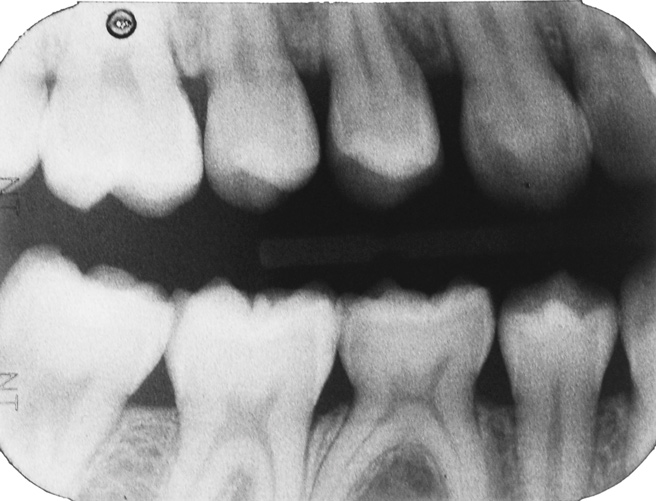

Interproximal insertion of SDF is demonstrated in different patients in Figure 3 through Figure 11. Various diameters and brands of soft dental picks may be used depending on the closeness of the proximal surfaces and ease of insertion; for example, some picks are designed for use in wider spaces between teeth. This protocol also offers versatility. Figure 3, for example, shows the simultaneous use of three thin soft dental picks to saturate proximal surfaces with SDF in a teenaged patient; the treated regions were subsequently covered with fluoride varnish (Figure 4). This patient was initially treated in April 2019 (Figure 5), with an identical re-application 3 months later. As shown in Figure 6, the December 2019 bitewing film revealed good results with the possible exception of the contact regions of the maxillary first and second molars. New SDF application was completed in the December appointment.

Fig 5. Three thin soft dental picks were used simultaneously for SDF proximal surface saturations in a teenaged patient (Fig 3). After 60 seconds, the treated regions were covered with 5% fluoride varnish (Fig 4). A comparison can be seen of pre-SDF-treatment bitewing films (Fig 5) and 8-month post-SDF bitewing films (Fig 6) for the patient shown in Fig 3 and Fig 4. Radiolucencies were similar or improved, except for contact of maxillary first and second molars.

Figure 5